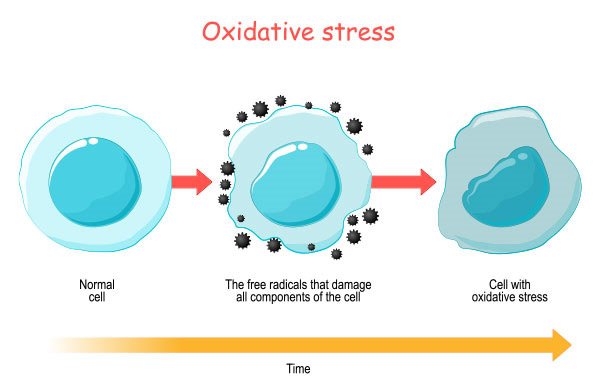

- Exposure to plastics has also been linked to an increased risk of cancer. This could occur as a result of the direct consequences of long-term plastic exposure or as a result of the other types of damage that plastics can cause. For instance, oxidative stress is a cancer risk factor.

- Oxidative stress occurs when the body’s antioxidants and free radicals are out of equilibrium. This could have far-reaching consequences for a person’s health, including an increased chance of catastrophic illnesses like cancer and heart attack.